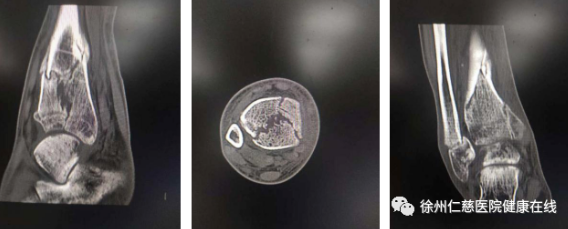

胡师傅来到betway在线登陆足踝外科,二病区徐明亮主任给他做了详细检查。踝关节骨折,没有复位固定,已经导致骨折畸形愈合,错过了手术最佳时机,后期可能导致创伤性关节炎。医生原本计划进行截骨矫形,但因患者的内外踝伤口未完全愈合,只能等待皮肤完全愈合了再手术。